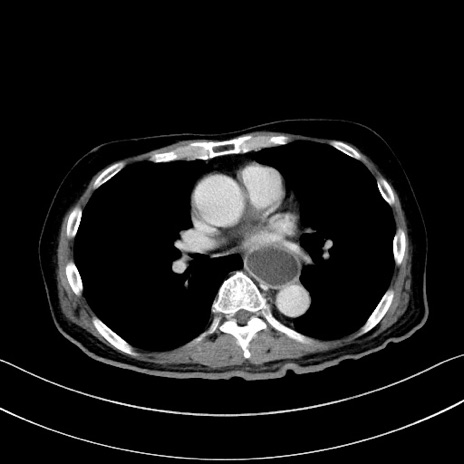

症例28(横断像)

【症例】60歳代男性

【主訴】嘔吐

【現病歴】胃癌にて胃全摘後。食思不振が悪化し、夜中に嘔吐することがある。

【既往歴】胃癌、胃全摘、脾摘、胆摘後

【データ】WBC 5900、CRP 10.56